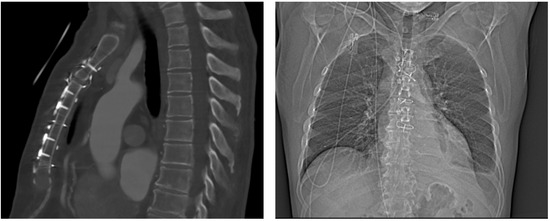

4.1.1. Case 1

4.1.2. Case 2